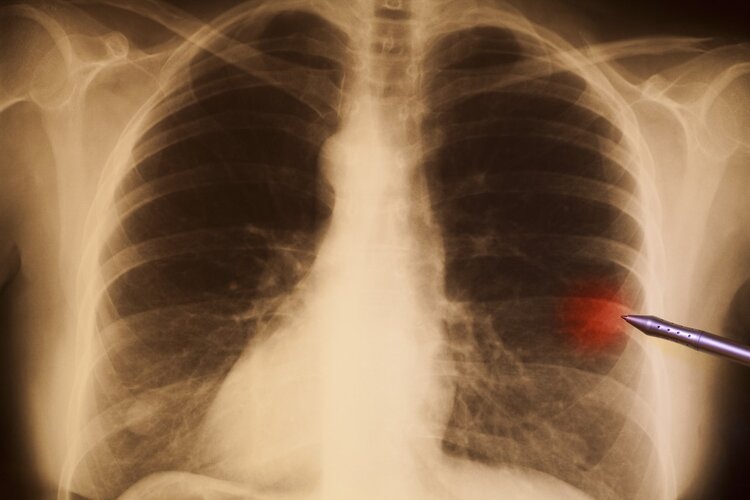

四、长期咳嗽 , 小心肺癌

今年三月份 , 李洁出现频繁咳嗽的情况 , 最开始以为是普通感冒 , 就没在意 , 过了一个月 , 李洁发现肩膀开始出现疼痛 , 而且咳嗽时还会有带血丝的痰排出来 , 这可把她吓坏了 , 李洁的老公赶紧带她去医院 。

然后检查结果把李洁吓瘫在地上:肺癌 。